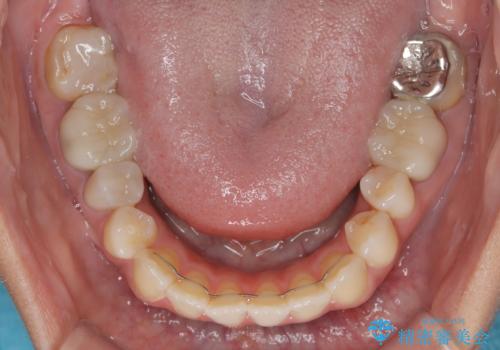

開咬と前突を改善 ワイヤー装置での抜歯矯正

結果として下顎の小臼歯は抜歯せず、右上の抜歯スペースはむし歯処置を兼ねてオールセラミックブリッジにて補綴治療を行うこととしました。

動かない歯での停滞や、出産と子育てなどにより治療期間は長期化しましたが、整った歯列にて仕上げることができました。